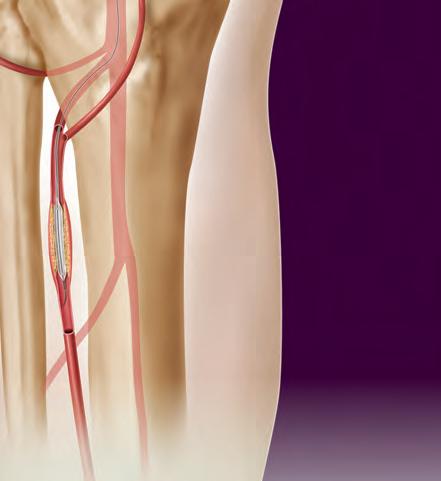

Carotid artery disease higher in the neck may be difficult to treat with CEA.

TCAR may be your option. With thousands of real world patients studied, TCAR has shown to be a safe and clinically effective alternative to CEA. A high cervical lesion in the carotid artery

Other patients who could benefit from carotid revascularization through robust reverse flow include:*

• SURGICALLY INACCESSIBLE LESION

LESIONS ACROSS THE ELBOW

Thrombosed AV grafts

Complex iliac lesions

In-stent restenosis of the SFA

PTA failures of AV graft lesions

Long SFA lesions

Chronic total SFA occlusions

Physicians are achieving durable outcomes across the elbow with fewer reinterventions in rapidly failing AV access circuits. See the NEW case study at goremedical.com/viabahn/elbow

INDICATIONS FOR USE IN THE U.S.: The GORE® VIABAHN® Endoprosthesis is indicated for improving blood flow in patients with symptomatic peripheral arterial disease in superficial femoral artery de novo and restenotic lesions up to 270 mm in length with reference vessel diameters ranging from 4.0 –7.5 mm, in superficial femoral artery in-stent restenotic lesions up to 270 mm in length with reference vessel diameters ranging from 4.0 – 6.5 mm, and in iliac artery lesions up to 80 mm in length with reference vessel diameters ranging from 4.0 – 12 mm. The GORE® VIABAHN® Endoprosthesis is also indicated for the treatment of stenosis or thrombotic occlusion at the venous anastomosis of synthetic arteriovenous (AV) access grafts.